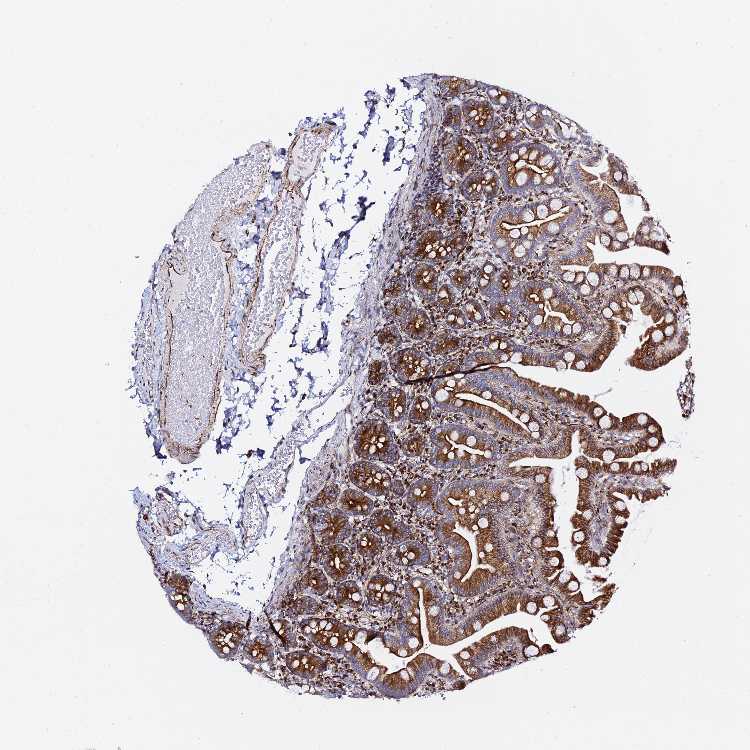

SMALL INTESTINE - Antibody stainingi

Antibody staining in the annotated cell types in the current human tissue is reported as not detected, low, medium, or high, based on conventional immunohistochemistry profiling in selected tissues. This score is based on the combination of the staining intensity and fraction of stained cells.

Each image is clickable and will lead to virtual microscopy that enables deeper exploration of all samples and also displays staining intensity scores, fraction scores and subcellular localization as well as patient and tissue information for each sample.

Antibody HPA043684Antibody HPA063394Antibody CAB046031

Glandular cells MediumMediumHigh